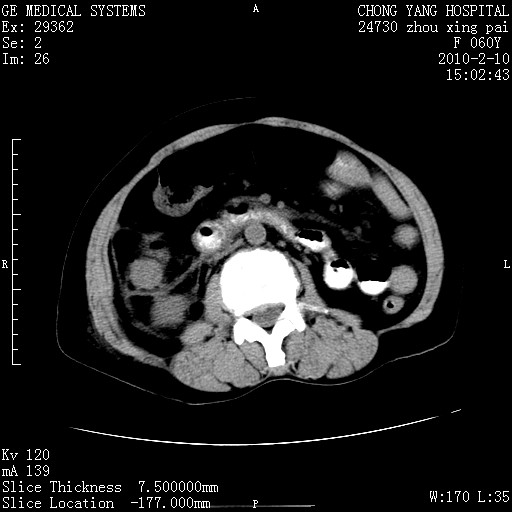

标题: CT24682:F60Y 腹痛 其它不详 [打印本页]

标题: CT24682:F60Y 腹痛 其它不详

胆总管末端梗阻!结石?肿瘤?建议增强!必要时行ercp!

胆总管末端梗阻!结石?胰腺影增粗,以胰腺头部为著,胰周看见渗出影,双侧胸腔积液,(胸膜反应)考虑胰腺炎。

1)胆总管末端梗阻,不排除结石所致可能。2)胰腺炎。3)慢性胆囊炎可能。4)左侧输尿管上段扩张。5)少量腹水。6)双侧少量胸腔积液,伴两下肺部分肺萎陷。

1)胆囊炎。2)胆源性胰腺炎。3)右肾周筋膜增厚,肾旁前间隙积液。4)左侧输尿管上段扩张。5)少量腹水。6)双侧少量胸腔积液,伴两下肺部分肺膨胀不全。

急性胰腺炎所致胆总管扩张!

1)胆总管末端梗阻。2)胰腺炎。3)慢性胆囊炎可能。4)左侧输尿管上段扩张。5)少量腹水。6)双侧少量胸腔积液,伴两下肺部分肺萎陷。